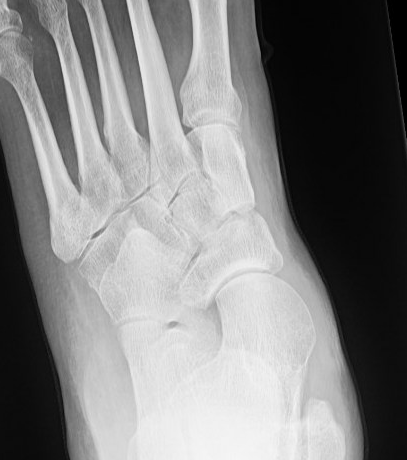

AP weight bearing foot

Talonavicular uncovering > 40% - forefoot abduction / stage IIB